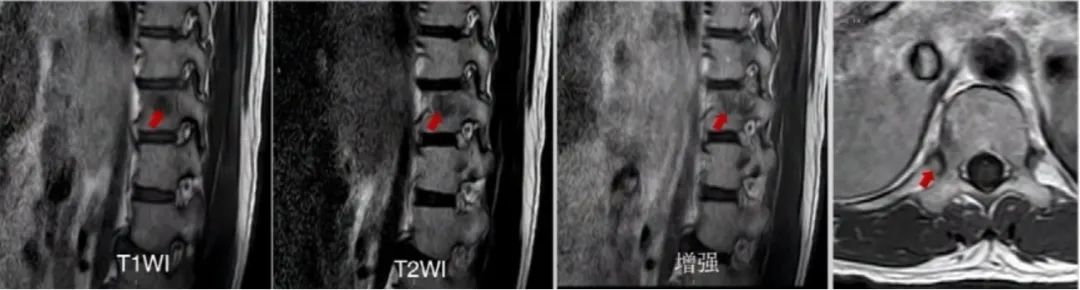

胸椎增强MRI:T11椎体及右侧第11肋骨头异常信号,考虑转移瘤。

PET/CT:升结肠癌术后,对比2019.1.24 PET/CT:结肠吻合口未见明显肿瘤复发征象;上次检查所见乙状结肠及直肠多发肿瘤病灶,本次检查未见显示;肝转移术后、综合治疗后表现:腹膜后区及右侧髂血管旁少许小淋巴结,代谢未见异常,考虑为淋巴结转移治疗后处于抑制状态,与上次检查比较病灶数量减少,代谢减低;右侧后胸膜病灶周围胸11椎体右侧缘新发成骨性骨质破坏。

2020.1术后病理

(胸11椎体+右侧第11肋骨头)骨髓腔内及纤维脂肪组织内可见少许癌组织,结合临床病史符合转移性结肠腺癌。

免疫组化结果:CK(+),CDX-2(-)。